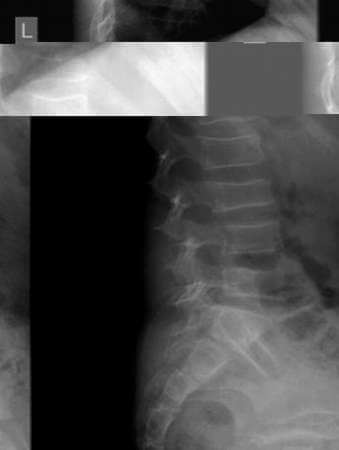

Οστεοπόρωση

Εικόνα Οστεοπόρωση στην ΟΜΣΣ με αμφίκοιλη διαμόρφωση στα οστά

Σε προσβολή της ΣΣ, εκδηλώνεται με οστεοπορωτικά κατάγματα των σπονδύλων που εμφανίζουν καθίζηση. Σε προσβολή του ισχίου, εμφανίζεται έντονη οστεοπόρωση στην πύλεο και στα μηριαία, κύρια στις μεταφύσεις, ενώ η διάφυση των οστών δεν προσβάλλεται.